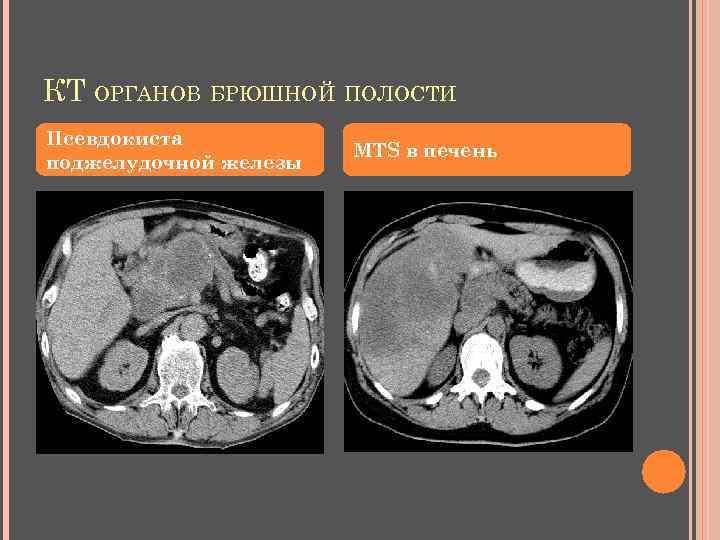

КТ ОРГАНОВ БРЮШНОЙ ПОЛОСТИ Псевдокиста поджелудочной железы MTS в печень